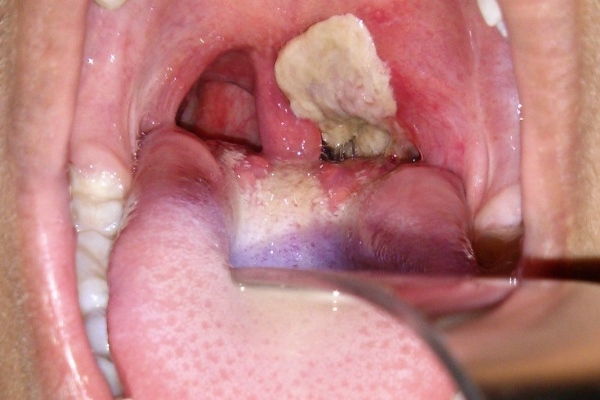

Дифтерия

Симптомы:

повышенная температура тела до 38°С, болезненные ощущения в горле, отек носоглотки, покраснение миндалин. На второй день в горле появляется налет, а на миндалинах формируются пленки. Также может наблюдаться отек подкожной клетчатки шеи.

Как выглядит заболевание:

Развитие болезни:

возбудителем является бактерия, вызывающая дифтерию, которая проникает в верхние дыхательные пути, поражая горло и лимфатические узлы. Характерной чертой является образование дифтерийной пленки в ротовой полости. Обычно через 6-10 дней заболевание начинает ослабевать. В остром течении у ребенка в первый день могут образоваться многочисленные пленки во рту, а горло сильно отекает. Без оказания первой помощи возможен летальный исход через 2-3 дня.

Возраст:

от 1 года до 13 лет.

Инкубационный период:

от 2 до 11 дней (чаще всего 3-5 дней).

Осложнения:

круп,

инфекционно-токсический шок.

Лечение:

самостоятельное лечение недопустимо, требуется исключительно госпитализация.